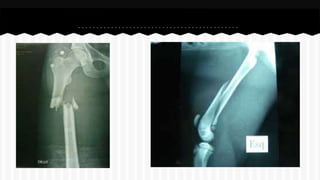

RESPONDA O NOME DO OSSO EM QUE

SE ENCONTRA A (S) FRATURA (A).